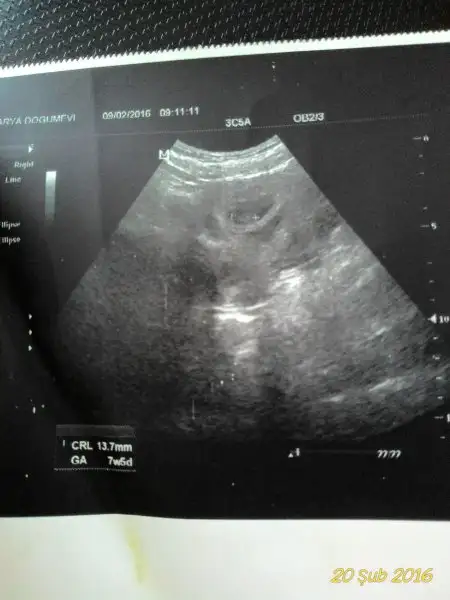

Arkadaşlar adete göre 7+2 usg ye göre 6+5 lik bebeklerim. :) daha önce erkek demişti arkadaşımız eşimin isteğiyle bir kez daha soruyorum size. :)

Eklentiler

• 20160220_095801-1.webp

9,4 KB · Görüntüleme: 198